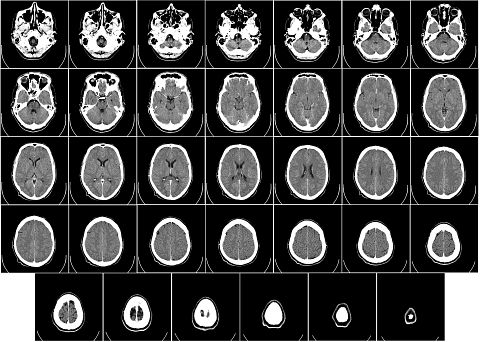

Radiation therapists administer radiation treatment to help fight cancer, including monitoring patients’ progress and reporting this data to the proper medical professionals. They help patients to understand how radiation therapy works by providing explanation and answering questions. They must have the ability to perform X-rays, operate a variety of medical equipment, and report any equipment malfunctions.